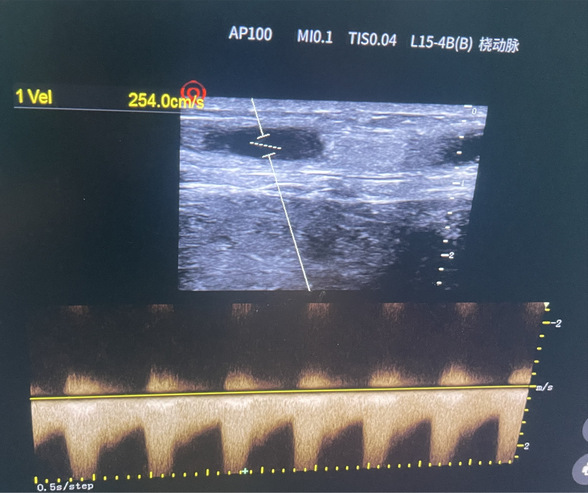

术后第二天上机透析流量

经手术室、麻醉科、导管室的通力合作,患者于当日18时顺利进入手术室进行上臂神经阻滞麻醉下行超声引导内瘘狭窄球囊扩张成形+鞘内溶栓术。经过2小时40分的紧张手术,患者闭塞内瘘顺利开通震颤恢复。次日透析血流量230ml/mim,满足透析要求,患者及家属悬着的心终于可以放下了。